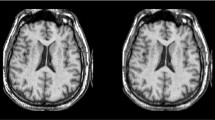

In this paper, we describe a medical image fusion technique based on relative total variation decomposition (RTVD) that can concurrently maintain the texture and contrast information of the input images. The source images are initially separated into structural and texture components based on the relative total variation. The former is mostly composed of the large frame structure and brightness of the source images, while the latter is composed of the texture and noise with low gradient values. Second, distinct fusion weights are created utilizing traits of the structure and texture layers. To maintain the texture information, the weights of texture parts are calculated in accordance with the saliency map, and the weights of structure parts are established in accordance with image energy to maintain the brightness of original images. The fused image could eventually be recreated utilizing sub-images and weights that were previously gathered. We also conduct qualitative and quantitative experiments to verify the effectiveness of the RTVD approach utilizing publically accessible datasets. The findings demonstrate that the RTVD fusion technique performs better than various more sophisticated algorithms in terms of maintaining contrast, preventing edge blurring, and lowering noise. The fusion outcome also more closely matches disease diagnosis.